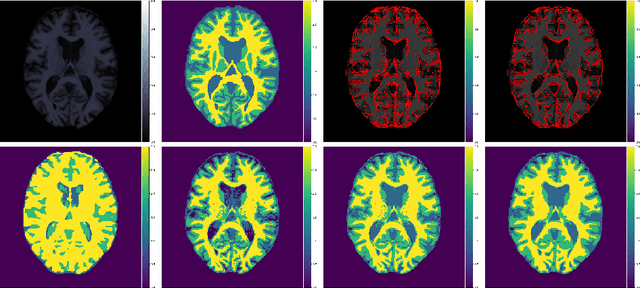

Abstract:In a broad range of fields it may be desirable to reuse a supervised classification algorithm and apply it to a new data set. However, generalization of such an algorithm and thus achieving a similar classification performance is only possible when the training data used to build the algorithm is similar to new unseen data one wishes to apply it to. It is often unknown in advance how an algorithm will perform on new unseen data, being a crucial reason for not deploying an algorithm at all. Therefore, tools are needed to measure the similarity of data sets. In this paper, we propose the Data Representativeness Criterion (DRC) to determine how representative a training data set is of a new unseen data set. We present a proof of principle, to see whether the DRC can quantify the similarity of data sets and whether the DRC relates to the performance of a supervised classification algorithm. We compared a number of magnetic resonance imaging (MRI) data sets, ranging from subtle to severe difference is acquisition parameters. Results indicate that, based on the similarity of data sets, the DRC is able to give an indication as to when the performance of a supervised classifier decreases. The strictness of the DRC can be set by the user, depending on what one considers to be an acceptable underperformance.

Abstract:Suppose one is faced with the challenge of tissue segmentation in MR images, without annotators at their center to provide labeled training data. One option is to go to another medical center for a trained classifier. Sadly, tissue classifiers do not generalize well across centers due to voxel intensity shifts caused by center-specific acquisition protocols. However, certain aspects of segmentations, such as spatial smoothness, remain relatively consistent and can be learned separately. Here we present a smoothness prior that is fit to segmentations produced at another medical center. This informative prior is presented to an unsupervised Bayesian model. The model clusters the voxel intensities, such that it produces segmentations that are similarly smooth to those of the other medical center. In addition, the unsupervised Bayesian model is extended to a semi-supervised variant, which needs no visual interpretation of clusters into tissues.

Abstract:Generalization of voxelwise classifiers is hampered by differences between MRI-scanners, e.g. different acquisition protocols and field strengths. To address this limitation, we propose a Siamese neural network (MRAI-NET) that extracts acquisition-invariant feature vectors. These can consequently be used by task-specific methods, such as voxelwise classifiers for tissue segmentation. MRAI-NET is tested on both simulated and real patient data. Experiments show that MRAI-NET outperforms voxelwise classifiers trained on the source or target scanner data when a small number of labeled samples is available.